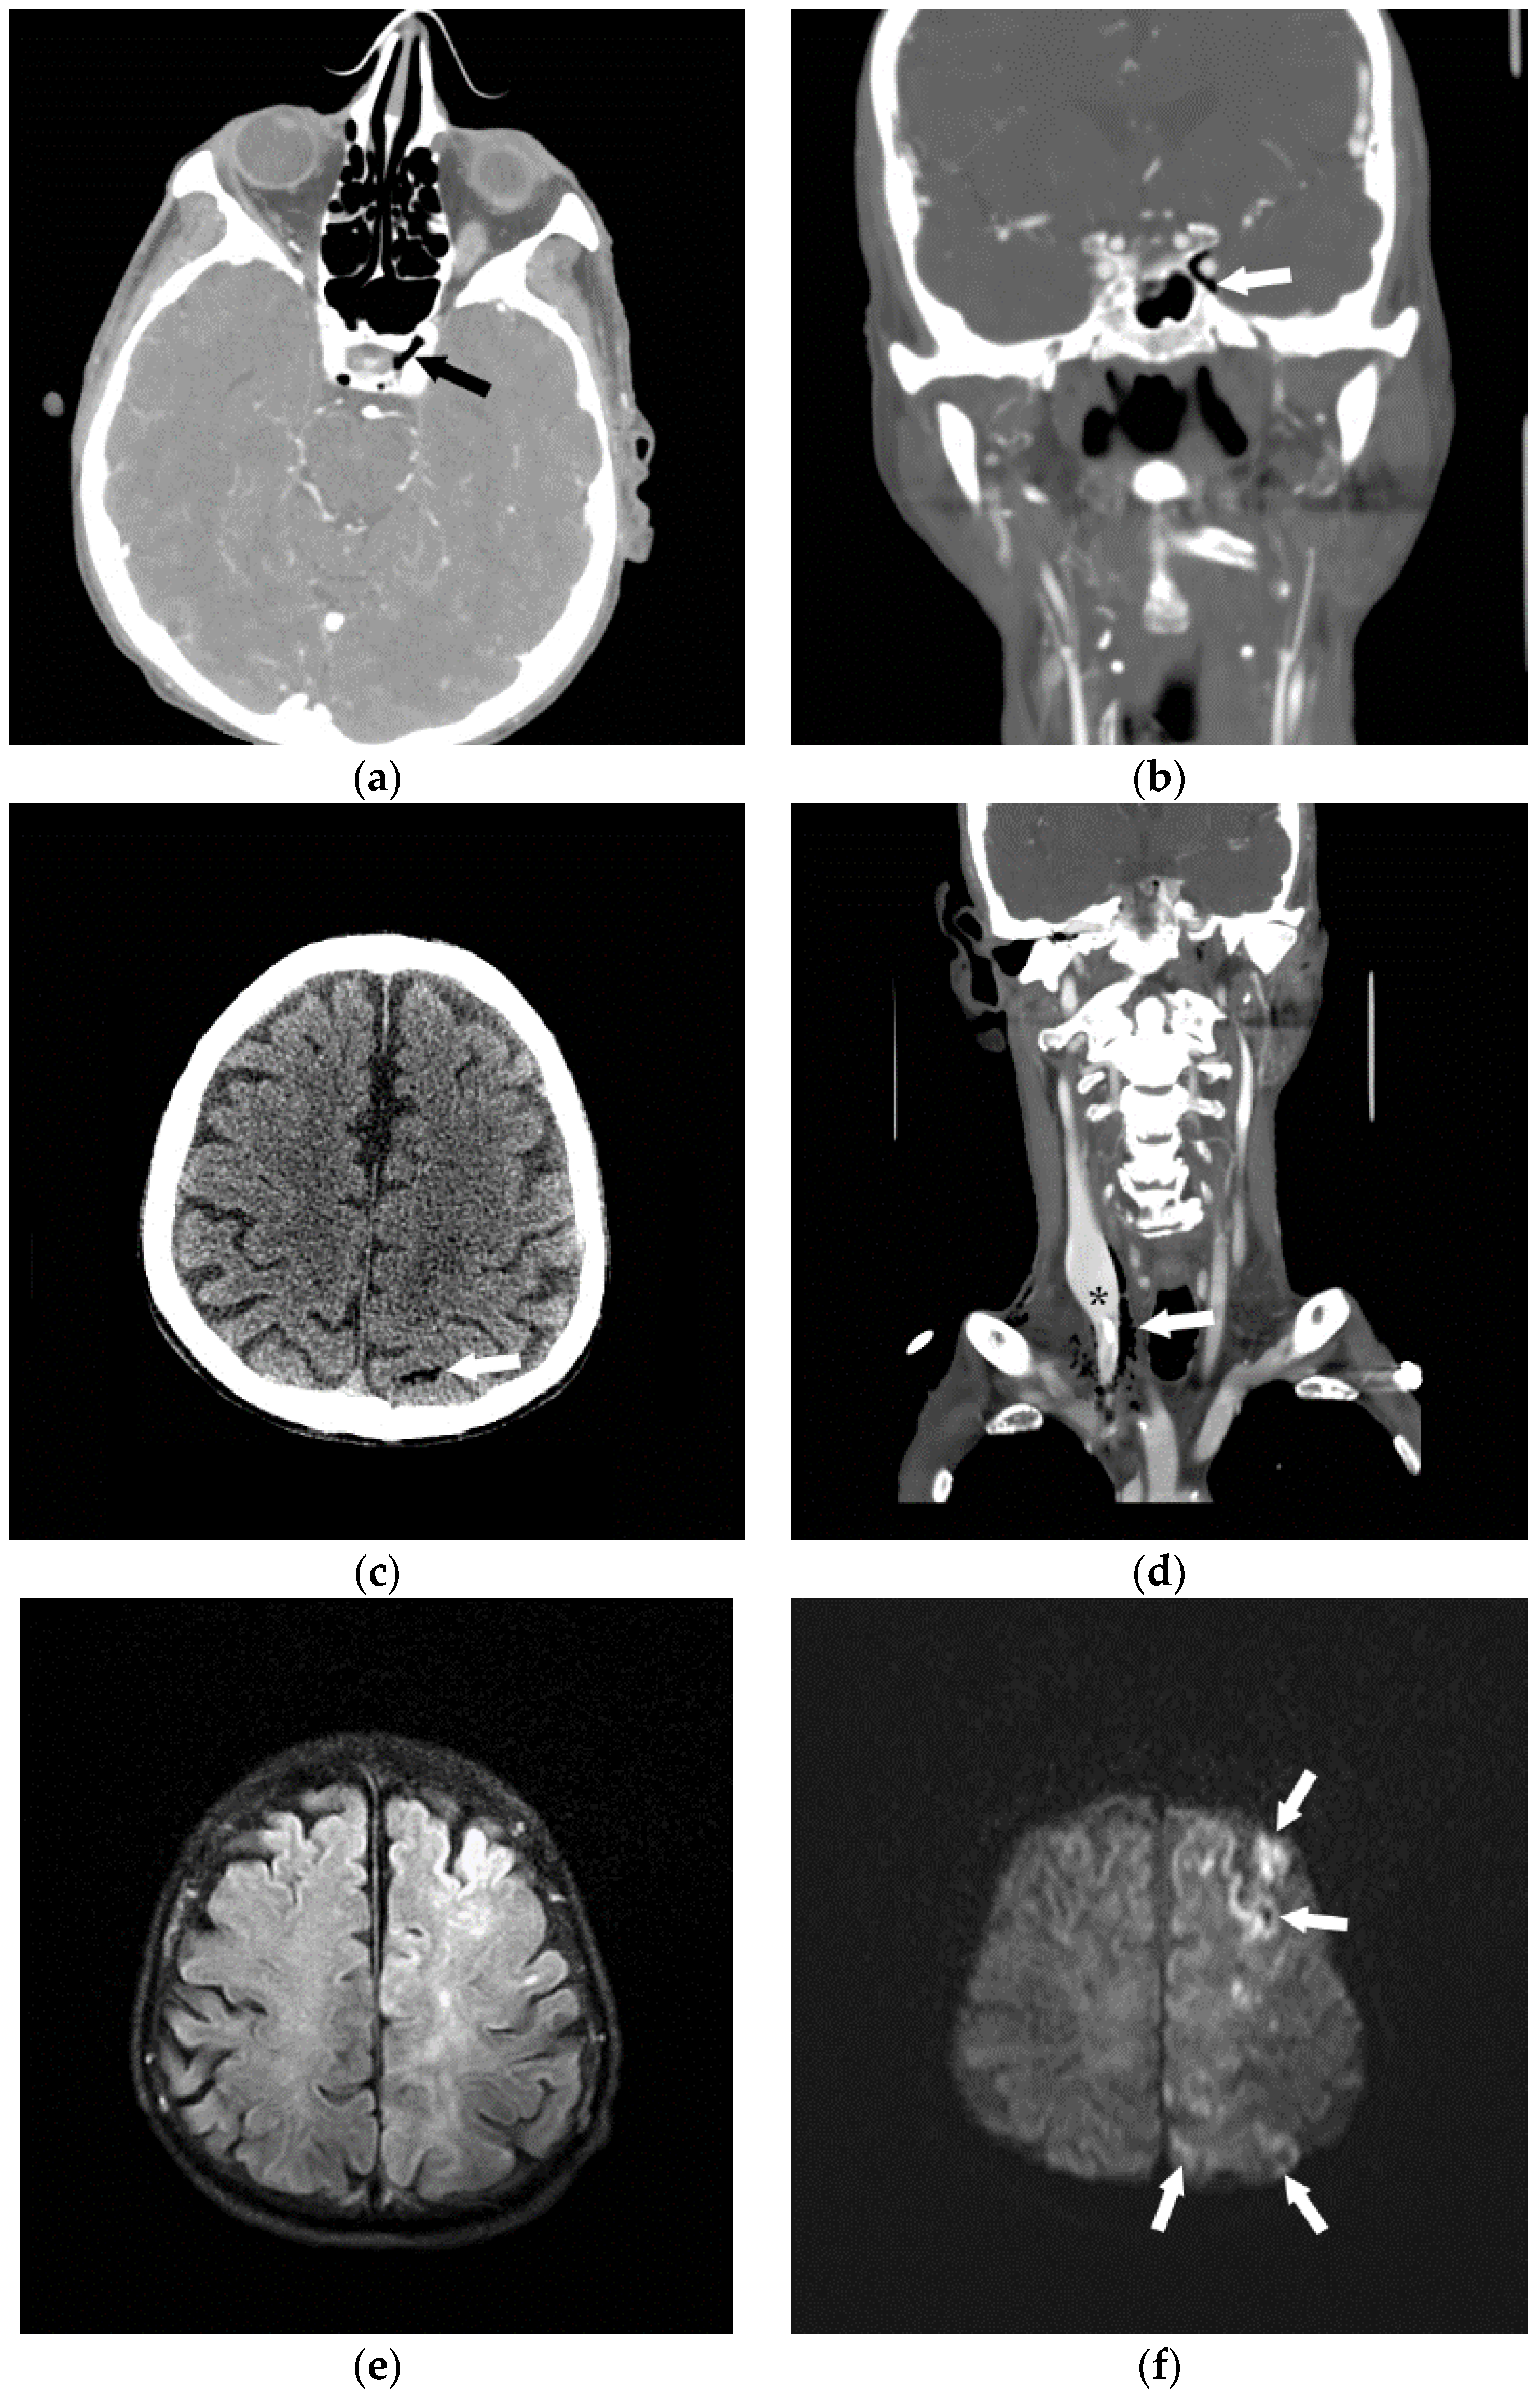

Figure 4.

Following the placement of right internal jugular tunneled Hickman line, a 76-year-old man developed an episode of desaturation, tachycardia, and non-responsiveness. Subsequently, an immediate CT of brain, neck and chest was performed and gas was found in the left cavernous sinus (a,b) and within a left parietal sulcus (c); it was felt to represent air in a vessel, possibly a pial vein. There was also a large amount of air surrounding the right internal jugular vein (d); with a partially visualized central venous catheter (*). A brain MRI was performed showing FLAIR hyperintensity in multiple regions (e) with evidence of restricted diffusion (f); and corresponding low signal (arrowheads) on the apparent diffusion coefficient (ADC) images (g). The patient received a single treatment of hyperbaric oxygen but died 8 days later.